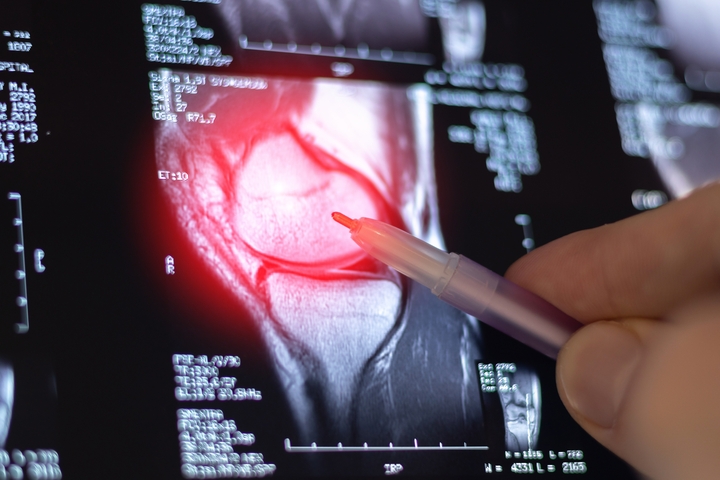

The first step to a life with less pain is a comprehensive consultation with our expert medical team. During your visit, we will perform a thorough physical examination, review any imaging (like X-rays or MRIs), and discuss your medical history and lifestyle goals. This allows us to determine if you are a suitable candidate for biologic therapy and to create a personalized treatment plan designed for your specific needs.